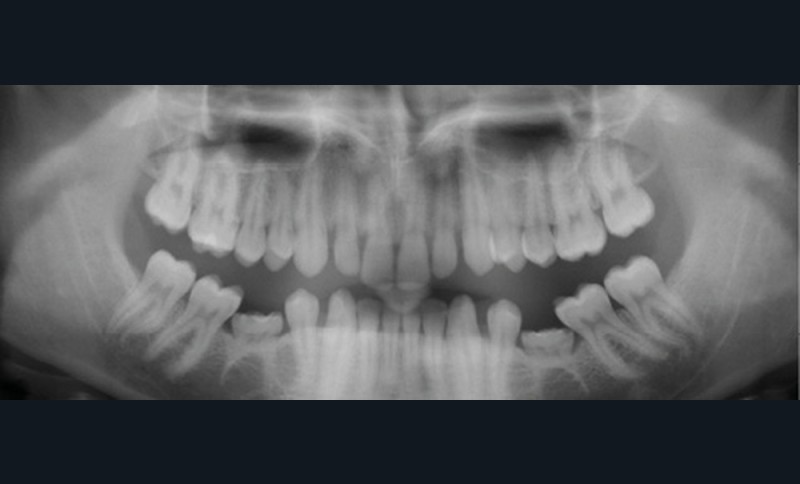

Quand un traitement orthodontique est indiqué dans le cadre de la persistance d’une molaire temporaire, l’orthodontiste doit toujours choisir entre deux solutions : maintenir ou fermer l’espace d’agénésie. Malheureusement, il est parfois confronté à une indication de maintien de l’espace d’agénésie, alors que la dent temporaire ne peut pas être maintenue jusqu’à la fin de la croissance (pour cause de caries, de réinclusion sévère, de perte, etc.) (fig. 1). La pose d’un mainteneur d’espace en fin de traitement est nécessaire, mais rien ne maintient l’os jusqu’à la fin de la croissance et la pose implantaire ! Les patients se retrouvent alors obligés de recourir à des préparations osseuses préimplantaires parfois lourdes. Le but de cet article est de proposer des solutions de maintien du volume osseux après avulsion de la deuxième molaire temporaire.